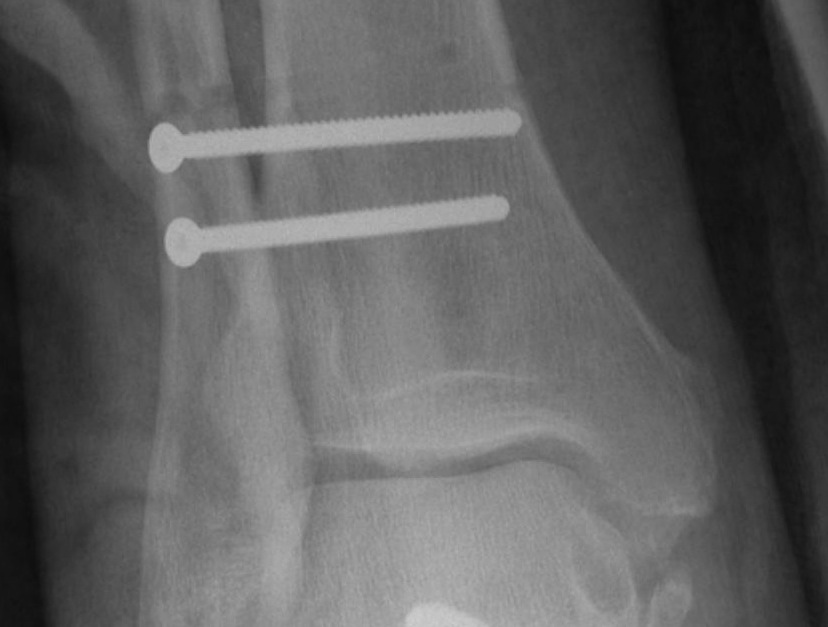

Screw fixation

Technique

AO surgery reference surgical technique

Open reduction of the distal tibio-fibular joint

Two screws

- level of syndesmosis (1.5 - 3 cm from joint)

- angle 30 degrees anterior

- 3 or 4 cortices

- 4 cortices probably more likely to break

- insert screws with ankle at neutral dorsiflexion

- consider removal at 4 - 6 months